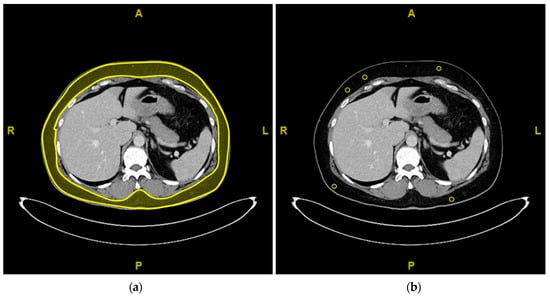

2.5. Objective Analysis of Image Quality

3.4. Images